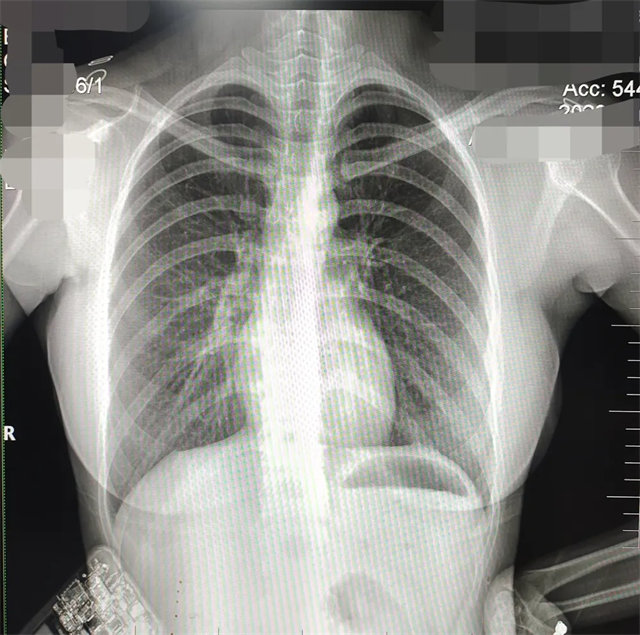

拍攝的不合格胸片的缺陷和解決方法

缺陷:兩肩胛骨未拉開肺野之外,吸氣不完全,且存在金屬飾品遮擋。

解決:去除金屬飾品及內(nèi)衣后重新按標(biāo)準(zhǔn)體位攝片即可。

缺陷:雙側(cè)胸鎖關(guān)節(jié)不對(duì)稱,且有手機(jī)顯影。

解決:去除手機(jī)后,使患者左側(cè)緊貼成像件曝光。

缺陷:左肩胛骨部分與左肺野重疊。

解決:使患者左肩旋前緊貼成像件重新曝光。

缺陷:肩胛骨未完全拉離肺野,吸氣不完全,存在金屬偽影遮擋,略有聳肩,且肺尖顯示不好,圖像顆粒感較強(qiáng),管電流量不夠,信噪比偏低。

解決:去除金屬物品后,按標(biāo)準(zhǔn)體位,使患者雙肩旋前與前胸一并緊貼成像件,適當(dāng)調(diào)高mAs,然后深吸氣后屏氣曝光。